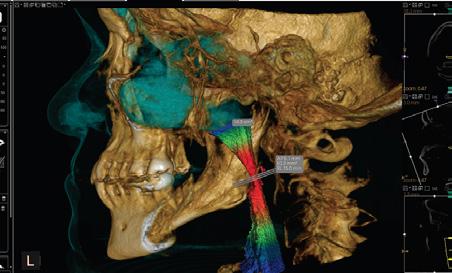

The next generation of DEXIS™ Cone Beam Technology is here

Simplify and expand your 3D diagnostics with the new ORTHOPANTOMOGRAPH™ OP 3D™ LX

Leading innovator of dental imaging technologies, DEXIS, has launched the next-generation OP 3D.

Built on OP 3D technology, the OP 3D LX imaging platform expands your 3D diagnostic capabilities with a wide range of clinical applications that support your evolving practice and enhance diagnostic confidence.

Consistent, high-quality images

Figure 4. Maxillofacial surgery. Figure 6. TMJ analysis. Figure 8. Airway analysis. Figure 10. Periodontics. Figure 5. Orthodontics. Figure 7. Implant placement. Figure 9. Prosthodontics. Figure 11. Endodontics.

landmarks, annotating mandibular nerve canals, tracing patientspecific panoramic curves for mandible and maxilla and merging CBCT and intraoral scan data for improved implant planning. These intuitive award-winning software features support a more efficient workflow allowing you to spend less time in the software and more time with your patient.